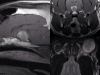

В рамках диагностики центральной-нервной системы собаке проводится МРТ головного и спинного мозга. Исследование с высокой точностью позволяет обнаружить новообразования и опухоли на ранних стадиях, оценить распространенность опухолевого процесса, выявить кровоизлияния, отеки и очаги компрессии и прочие аномальные изменения.

Данный метод неинвазивной диагностики часто применяется и для обследования опорно-двигательного аппарата. Проведение МРТ позвоночника собаке актуально при подозрении на воспаления или какие-либо патологические изменения в позвонках и межпозвоночных дисках. С помощью томографа исследуется состояние связок и суставов, мышц и сухожилий, диагностируются дегенеративные изменения, травмы, воспаления и опухоли.